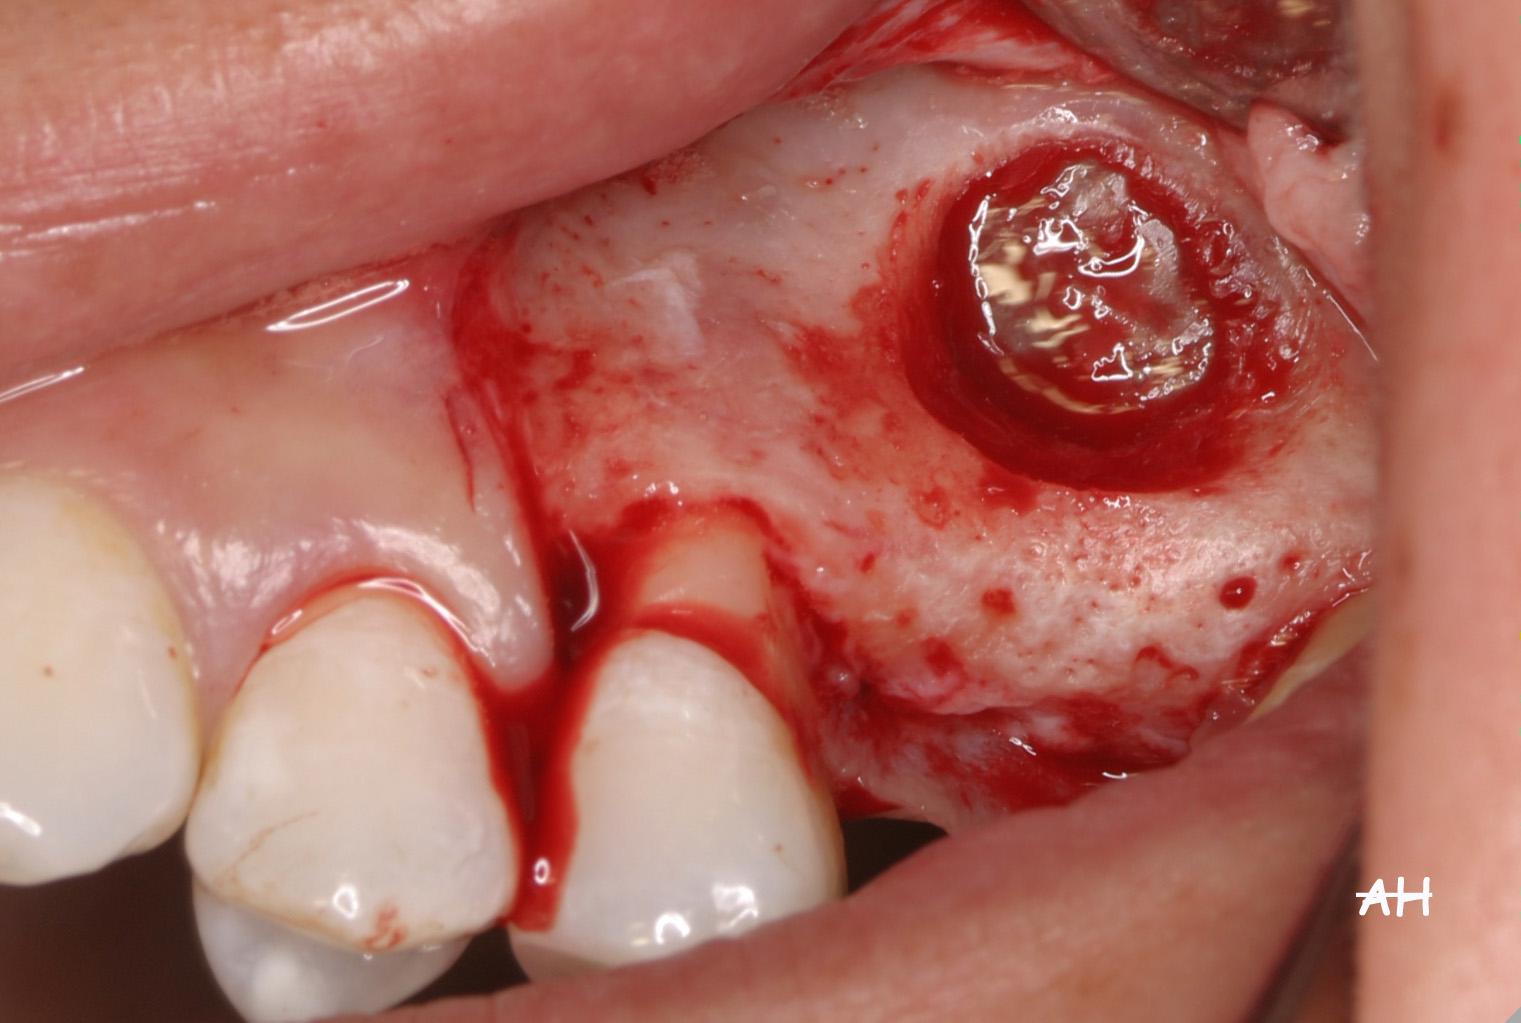

Exemple 11: Pendant l'implantation on remarque un manque d'os sur la partie externe, les spires de l'implant sont visibles.

Exemple 11: Une greffe d'os est effectuée afin de compenser l'épaisseur d'os manquante.

Exemple 11: Le tout est recouvert d'une membrane collagène.